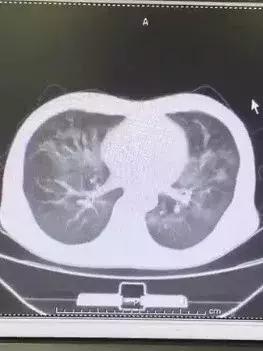

一周前,他咳嗽、高烧,当时拍的片子(普通x光胸片)考虑肺炎,所以发热门诊的医生开具了抗炎,退烧的药物。吃了两天之后,稍有好转,但每天下午还是会发烧,并且出现了逐渐加重的咳喘。

因为他来的时候已经吃过消炎药了,对于继续输液,我说,绝对不可以,然后他就哭了,真的,一个快50岁的老爷们儿在我的诊室哭了。如果不是因为急诊科病人陆续不绝,我真的可能多听一会:他的遭遇,上有老,下有小,孩子刚四岁,每天只有他接送,所以他不能住院......他的言行,让我总觉得哪里不对劲儿,事情好像没那么简单。“再去复查个CT吧,输液总不好也不是个事”。

胸部CT回报的结果显示,他的肺炎在逐渐加重,也就是说,消炎药对他效果甚微。我把他叫到诊室外,因为总有“我就插一句”的患者,虽然我不会让他们插一句,但是我要和他聊的内容不能有第三人在,要不确实不方便。